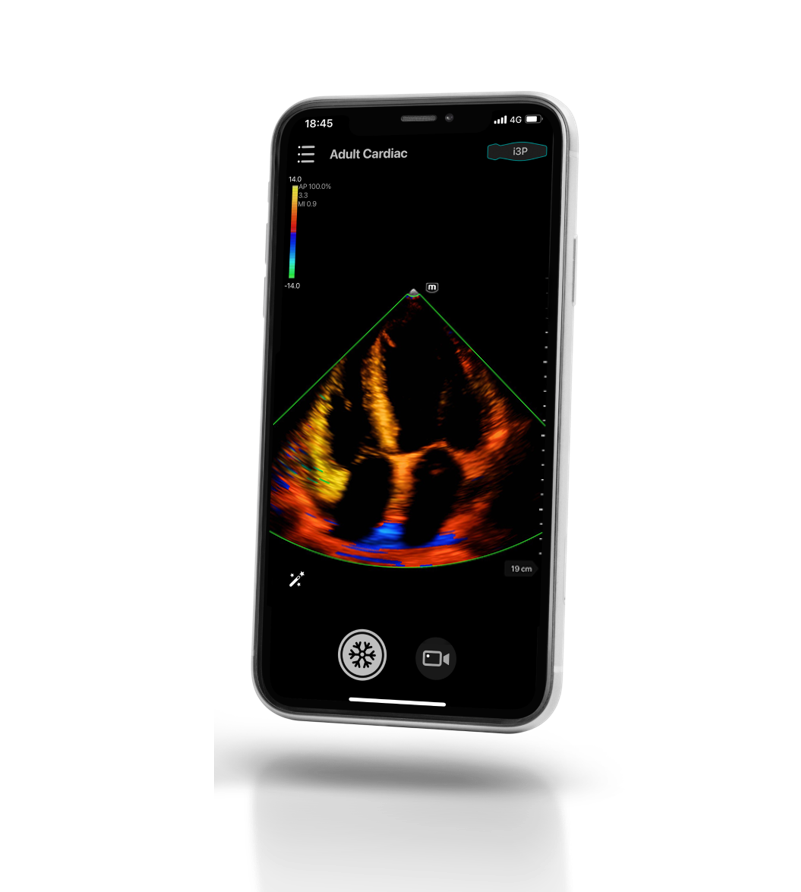

Oltre all'applicazione mobile, TE Air i3P puأ² essere collegato a dispositivi avanzati nell'ambito di assistenza d'emergenza e cure critiche, per offrire agli operatori sanitari un'esperienza piأ¹ creativa.

- Smartphone: valutazione facile e rapida

- Smartphone: valutazione facile e rapida

Salvataggio di immagine/video nell'APP TE Air i3P